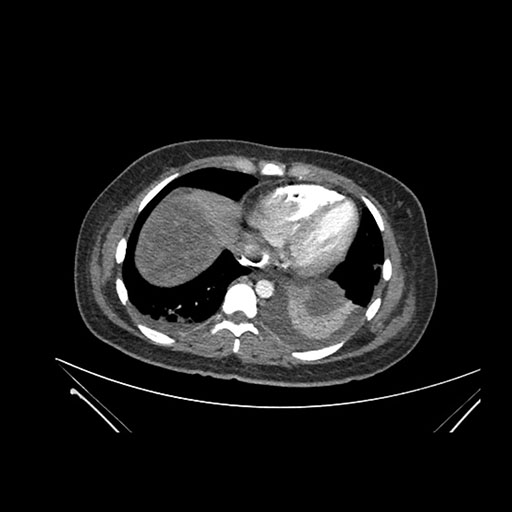

Imaging Analysis

Look through the patient's CT scan to identify any areas of concern for the necessary procedure.

Axial Arterial